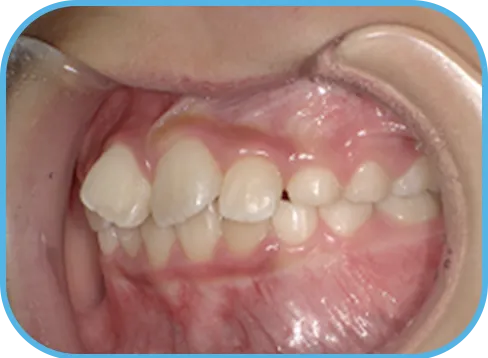

• 右 側

治療前右側からの歯の様子

治療後右側からの歯の様子

主 訴

上の前歯がねじれている、ガタガタ

治療内容

インビザライン・ファースト

治療期間

8か月

治療費(税別)

450,000円+診断料50,000円

リスク・副作用

• 親知らずの影響や加齢などによって、凸凹が生じる可能性があります。

• 治療の初期段階では痛みや不快感が生じやすくなりますが、1週間前後で慣れます。

• 顎の成長発育によって、噛み合わせや歯並びが変化する可能性があります。

• 状況により当初予定した治療計画を変更する可能性があります。